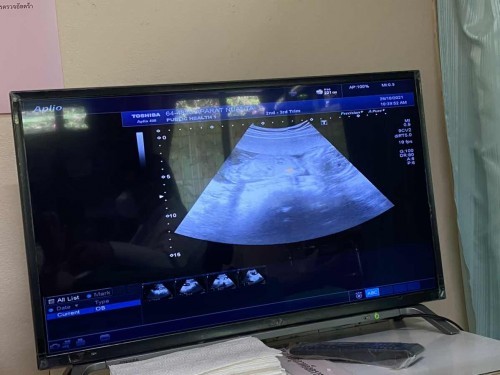

18 week 4 days ทีมมีนาคม ค่ะ ได้สาวน้อย ❤️ พิกัดเชียงใหม่ค่ะ 🥰🥰